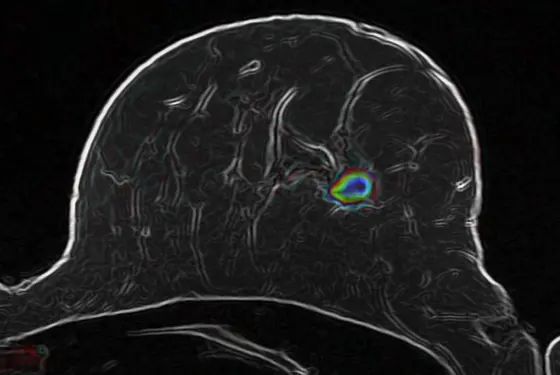

Optimized diffusion-weighted MR imaging (MRI) of a suspicious lesion in a female breast

Bickelhaupt and his colleagues have therefore optimized a method called diffusion-weighted MR imaging (MRI) for examining the female breast and combined it with intelligent computer-based image analysis methods. Diffusion-weighted MRI is a special technique that makes it possible to see the movement of water molecules in tissues and to observe it using a computer algorithm. Malignant tumors change the structure of tissues, thus causing changes in the movement patterns of water molecules. This link might be utilized in the early detection of breast cancer – without the necessity to take tissue samples or use contrast agents in the body. “Our goal is to obtain better noninvasive insight into the interior of the body and thus provide additional information about tissues for clinical evaluation by radiologists, along with the standard methods, which will continue to be relevant,“ said Bickelhaupt.

Their results were very promising: The new method enabled them to reduce the number of false positive findings in the study group by 70 percent. The scientists were able to identify truly malignant changes in 60 cases out of 61. This sums up to an accuracy of 98 percent and is comparable with the reliability of MRI methods that use contrast agents.